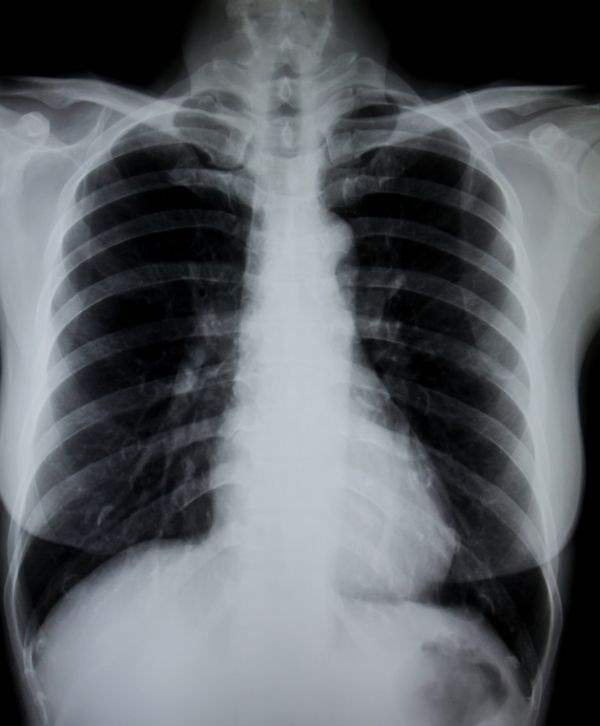

Bronşitin Teşhisi

Bronşiti bir üst solunum yolu enfeksiyonundan, sinüzitten ya da astımdan veya mideden gelebilecek bir reflü durumundan ayırmak gerekir. Doktor hastadan alacağı öyküyle hastada bronşit mi yoksa başka bir rahatsızlık mı olduğunu saptayabilir.

Bronşit astımla karışabilir. Eğer hastalık uzamışsa, astıma yol açan bronş hiperreaktivitesinin oluşup oluşmadığı araştırılır. Bunun için de solunum fonksiyon testleri yapılır. Durumun tespiti için bazen basit solunum fonksiyon testi yeterli olur.